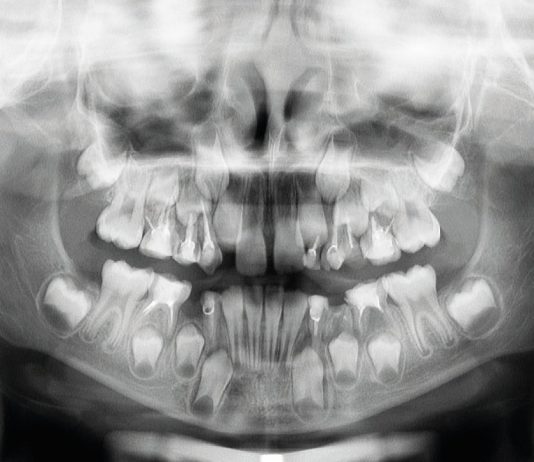

Gestione terapeutica di un paziente in crescita con scarsa igiene orale: trattamento pediatrico-ortodontico

Nel trattamento di casi clinici che necessitano di una gestione multidisciplinare in ambito pedodontico e ortodontico, è importante pianificare le varie fasi al fine...